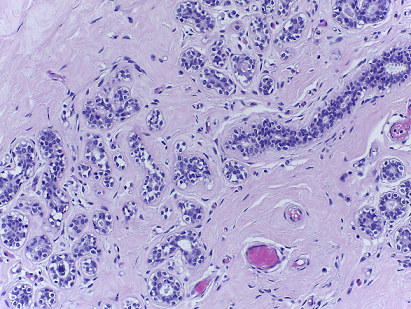

The microscopy dataset is composed of 400 training and 100 test images, with the four classes equally represented (see Fig. 2). All images were acquired in 2014, 2015 and 2017 using a Leica DM 2000 LED microscope and a Leica ICC50 HD camera and all patients are from the Porto and Castelo Branco regions (Portugal). Cases are from Ipatimup Diagnostics and come from three different hospitals (Hospital CUF Porto, Centro Hospitalar do Tâmega e Sousa and Centro Hospitalar Cova da Beira). The annotation was performed by two medical experts. Images where there was disagreement between the Normal and Benign classes were discarded. The remaining doubtful cases were confirmed via imunohistochemical analysis. The provided images are on RGB .tiff format and have a size of 2048×1536204815362048\times 1536 pixels and a pixel scale of 0.42 μ𝜇\mum ×\times 0.42 μ𝜇\mum. The labels of the images were provided in .csv format. Participants were provided with a partial patient-wise distribution of the images of the training set. The test data was collected from a completely different set of patients, ensuring a fairer evaluation of the methods. Note that the training set is an extension of the one used for developing the approach in [3].

Refer to caption

(a) Normal

(b) Benign

(c) In situ

(d) Invasive

Fig. 2: Examples of microscopy images from the BACH dataset.